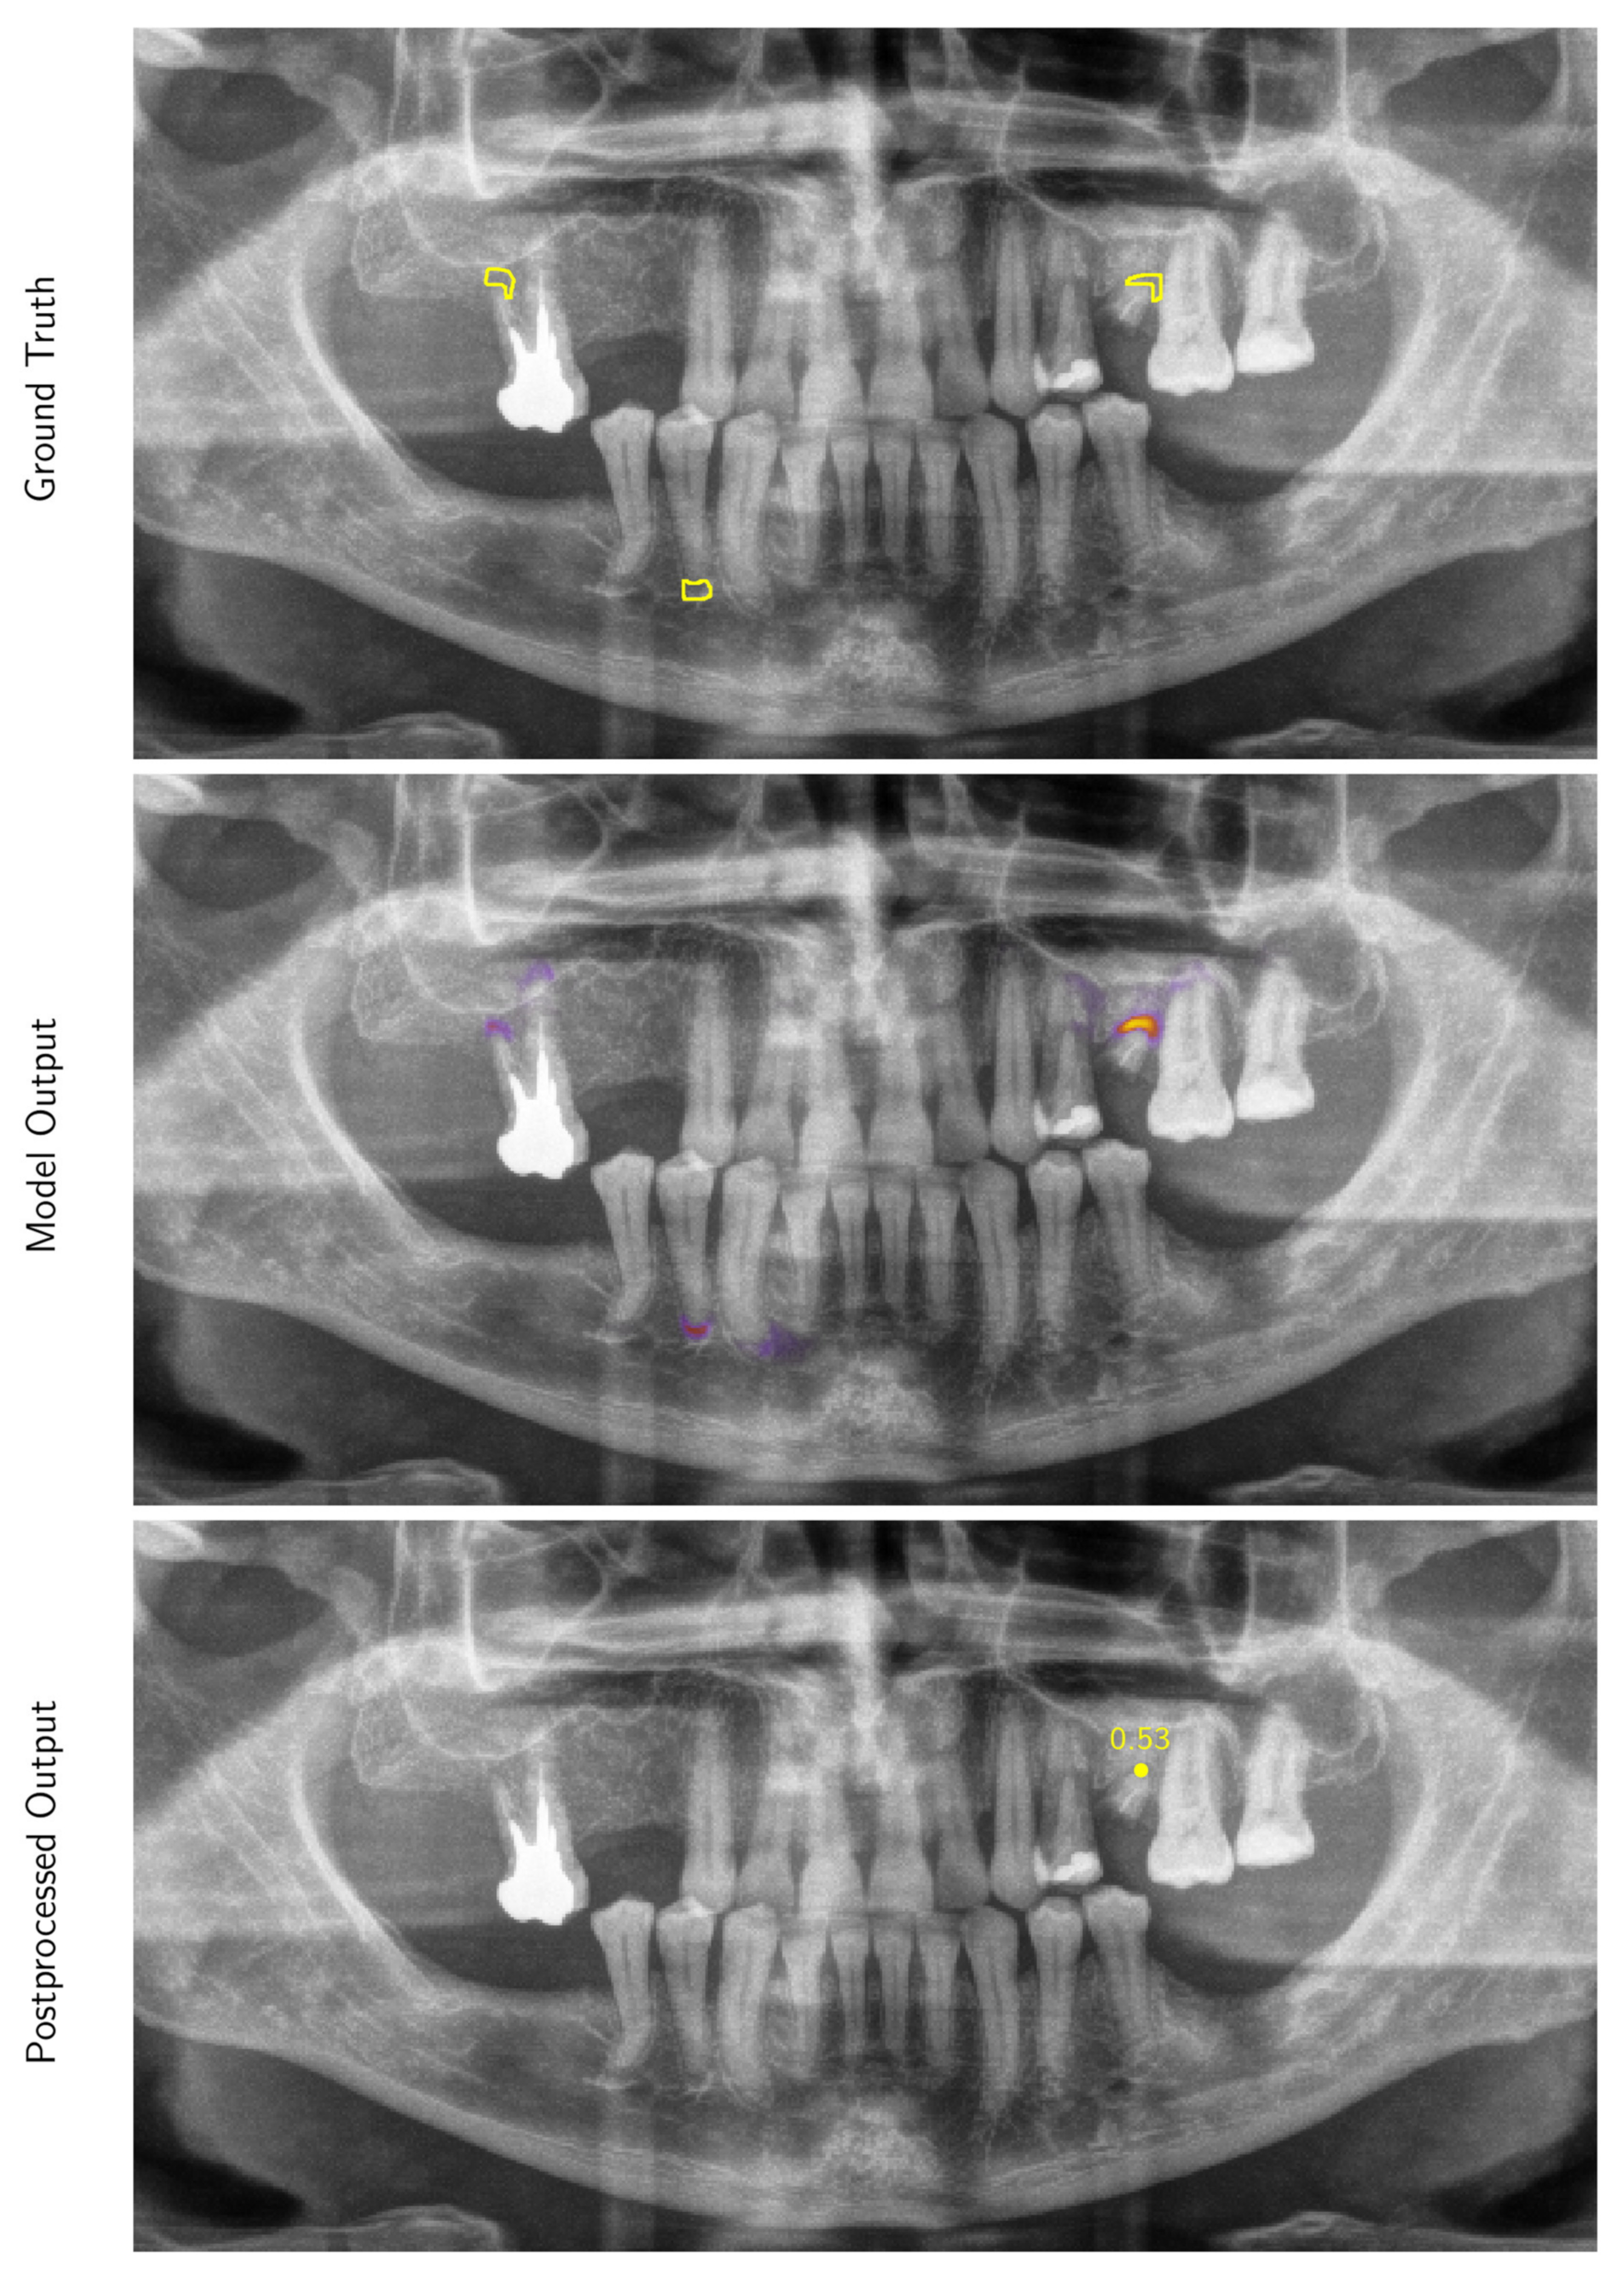

2.2. Development of a Deep Learning Algorithm for the Automated Detection of Periapical Radiolucencies in Panoramic Radiographs

Appendix A.1.2. Inference and Post-Processing